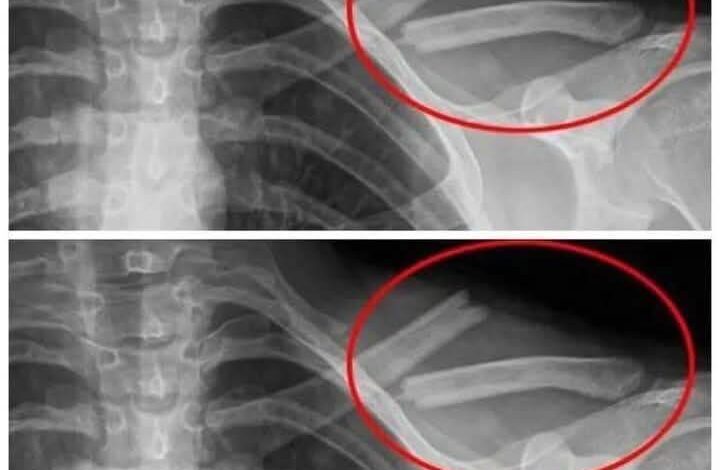

6. Bone Weakening: High soda intake depletes calcium, increasing osteoporosis risk.